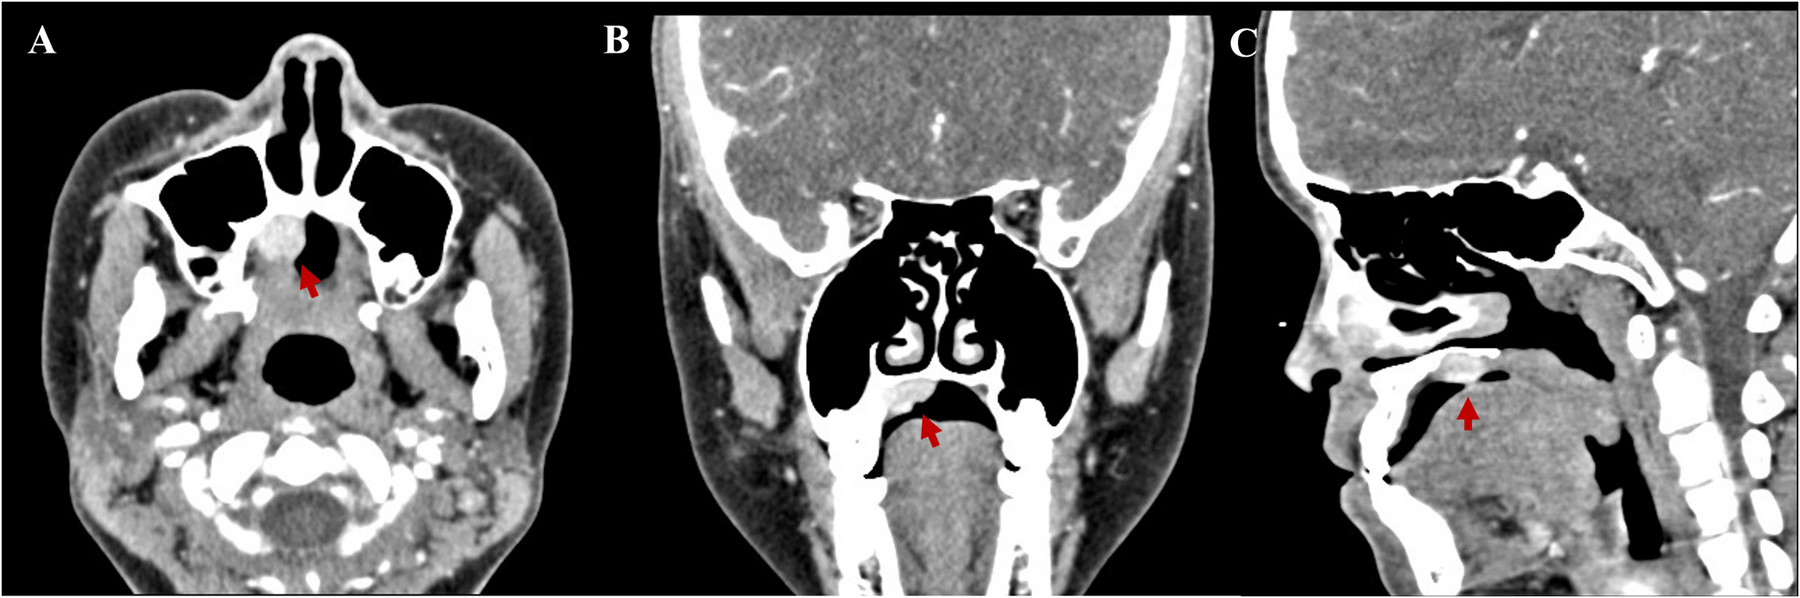

Contrast-enhanced computed tomography scans revealed a quasi-circular soft tissue mass of the right hard palate 1.5 cm × 1.2 cm × 1.0 cm in size. The mass was an enhancing nodular component, with probable bone remodeling but no definite bone invasion (Figure 1).

Figure 1. Contrast-enhanced computed tomography scans revealed a quasi-circular soft tissue mass of the right hard palate 1.5 cm × 1.2 cm × 1.0 cm in size. (A) Axial, (B) coronal, and (C) sagittal.